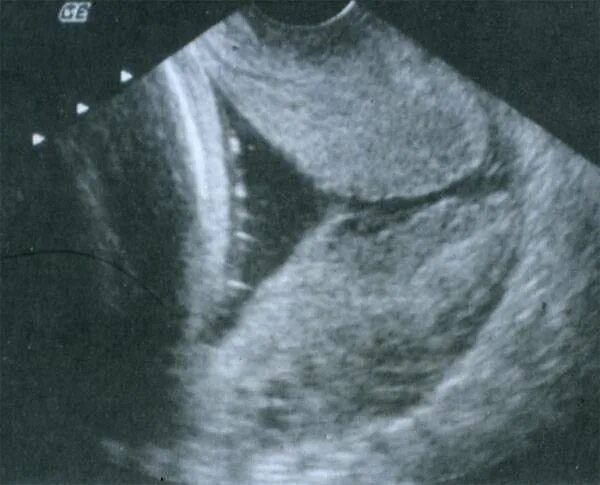

Зев т образный